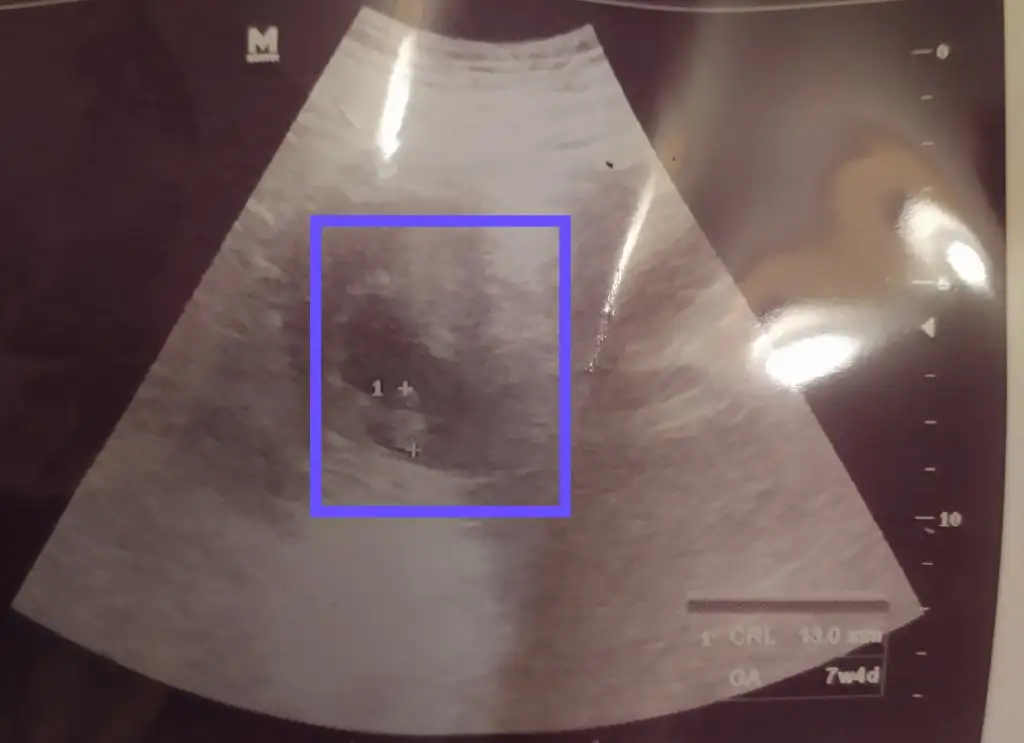

Canım seninle sat günlerimiz hemen hemen aynıydı bende dün 9 haftalık oldum pazartesi Dr a gittim ve bebeğim 9 hafta yerine 7+4 çıktı o kadar Üzüldüm ki geç döllenme falan olması imkansız daha önce gününde çıkıyordu şimdi senin görüntüyü görünce benimkide böyle olmalıydı dedim moralim çok bozuk acaba sürekli kustugum için mi böyle oldu başıma ilk kez böyle birşey geldi kendi Dr uma 12.hafta gidecem üç hafta yediklerime dikkat edeyim diyorum. Sana gelince ramziye göre erkek gibi geldi

Bak bu benimki 😪